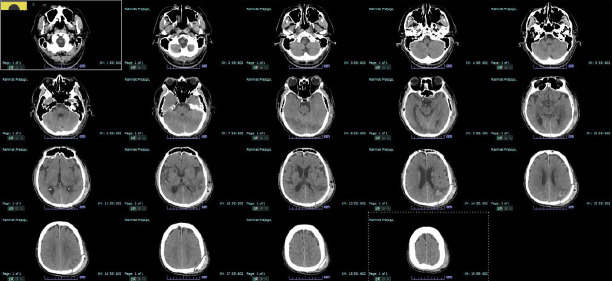

Optic aphasia is a rare neurological disorder that affects the visual-semantic ability of patients with normal vision and is caused by a lesion in the left occipital lobe. The signs and symptoms of optic aphasia are similar to those of associative visual agnosia, where patients have difficulty recognizing objects both in shape and function, resulting in challenges performing daily tasks. The transformation to optic aphasia or associative visual agnosia is closely related to the degree of damage to the corpus callosum, with some studies hypothetically suggesting that complete damage to the corpus callosum leads to optic aphasia, whereas incomplete damage causes associative visual agnosia. We present a case of a 60-year-old man with a history of intracerebral hemorrhage in the left occipitotemporoparietal lobe. The patient complained of intermittent episodes of painless, blurry vision. Upon examination, we observed that the patient was unable to read the Snellen chart, although he could draw the letter. Furthermore, we discovered that the patient had difficulty naming objects and instruments, even though he was able to express their shape and function through gestures and mimicry. The signs and symptoms of the patient, along with the result of the multi-slice non-contrast CT scan, suggest that he had optic aphasia rather than associative visual agnosia. A comprehensive neuropsychological and aphasia examination needs to be performed to further assess the condition of our patient and establish the diagnosis.

Abstract Image